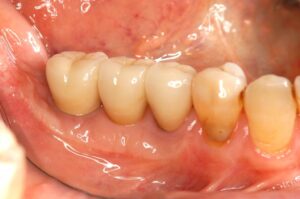

歯周病治療

歯周外科治療